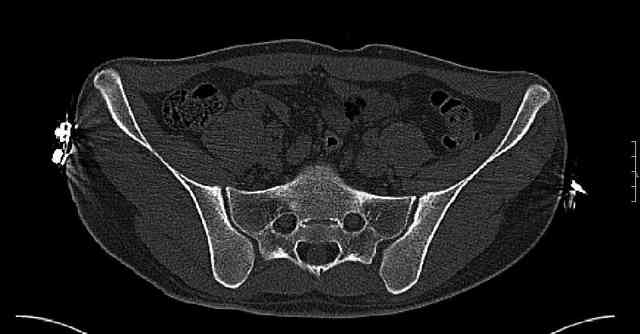

Re: Нелеченный перелом вертлужной впадины

Some more images. Does it help to guess which part of the acetabulum is displaced?